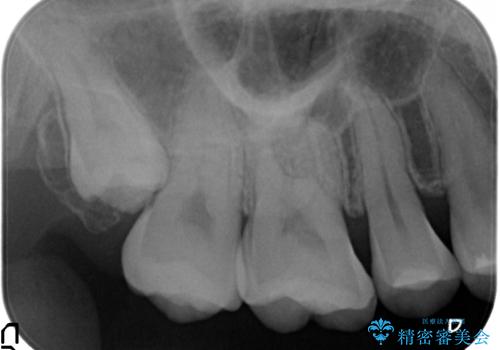

- 冷たいものを飲むと右上の奥歯がしみるので診て欲しいといらっしゃった方の症例です。

右上6番目、7番目の歯の樹脂が劣化していたため、虫歯除去後セラミックインレーによる修復を行いました。